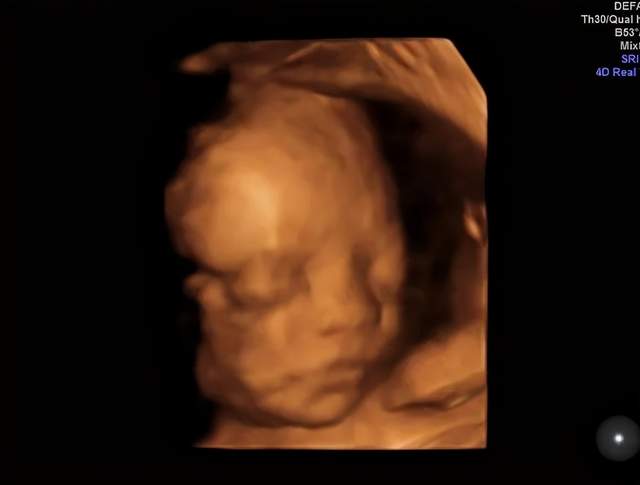

嗯,开始检查了!医生在妈妈肚子上涂了好多凉凉的东西,然后用一个小仪器在妈妈的肚子上探来探去。没多久,妈妈就看到了你的动态了哦!妈妈真的像在四维影院看电影一样的,看到你在肚子里各种欢腾的样子。

你看你爸爸,激动的一直说话,“老婆老婆!你看宝宝鼻梁多高,你看他还在吃手,你看他圆圆的脑袋好可爱啊……”宝贝,你爸爸是不是像个大孩子一样,看到你就手舞足蹈,语无伦次了。哈哈哈哈,你老爸让你一定要遗传他那活泼又搞笑的基因呢!

嘿嘿,下面照片就是你的“写真”,还是“裸体”的呢,不要害羞哈!这个可是爸爸妈妈送给你的礼物哦。等你长大了,看到在妈妈肚子里面的照片,是不是会很意外啊?嘿嘿,这个啊就是四维彩超的神奇功效啦,可以让爸爸妈妈看到你健健康康的成长,看到你欢快的动作还让爸爸妈妈稀里哗啦的留下了好多感动的眼泪呢。宝宝,爸爸妈妈等着你哦!

(转过来转过去,只为让医生和粑粑麻麻更清楚的看到我的盛世美颜)